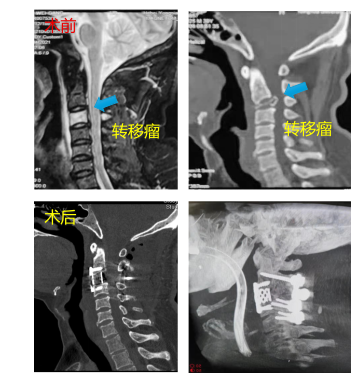

患者二、乳腺癌颈椎脊柱转移行肿瘤全切除+椎体重建内固定术

患者因乳腺癌转移到颈3椎体,颈部剧烈疼痛且难以抬头,肿瘤切除+重建固定术,术后疼痛消失,颈部支撑力恢复。